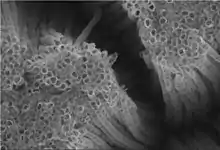

Les premières études publiées concernant l'application (in vitro et ex vivo) sur peau animale et peau humaine laissaient penser que les nanoparticules de TiO2 ne pénétraient que les couches externes de la peau (la couche cornée et l'infundibulum pilosébacé), mais ces études n'étaient pas représentatives de l'exposition réelle (études trop courtes, de 72 heures au maximum, utilisant des particules insuffisamment caractérisées en termes de « taille, forme cristalline, enrobage, etc. », voire sans protocoles standardisés ni validés, ou ne respectant pas les recommandations du Comité scientifique pour la sécurité des consommateurs (CSSC) ou de l'Organisation de coopération et de développement économiques (OCDE).

Puis une étude[46] publiée en 2010 a confirmé la présence (élevée dans ce cas) de nanoparticules de TiO2 (enrobées et non enrobées) et de particules de TiO2 submicroniques (300–500 nm) dans la couche cornée et moindrement (« quelques particules isolées » de TiO2 dans le derme pour les animaux traités avec les trois types de particules. Des « quantités statistiquement significatives de TiO2 » ont aussi été trouvées dans le ganglion inguinal gauche du groupe traité par des nanoparticules de TiO2 non enrobées et dans le ganglion inguinal droit du groupe traité par des particules de TiO2 submicroniques (300–500 nm). Les animaux ayant servi au test étaient des mini-porcs. L'application de crème était répétée « quatre fois par jour, cinq jours par semaine durant 22 jours ». Cette étude est considérée par l'Afssaps en 2011 comme la plus représentative des vraies conditions d'exposition. Une pénétration et une dispersion dans l'organisme semblent donc possibles chez l'humain (dont la peau est réputée fonctionner d'une manière proche de celle du mini-porc), au moins à partir des régions où la peau est la plus fine et perméable, et pour les cas où le TiO2 n'est pas sous forme « enrobée ». L'étude présente néanmoins un biais. Elle est faite sur des animaux adultes (peau plus épaisse) et à peau saine et non lésée. Elle ne permet pas de savoir si le comportement des nanoparticules est le même sur une peau de bébé ou d'enfant, ou sur une peau lésée par un coup de soleil, en train de peler, ou après une longue exposition aux UV, ou à la suite de lésions « de nature pathologique ou d'origine exogène » (par exemple, eczéma, psoriasis[47], impétigo, allergie, dermatite atopique[27]). Selon l'Afssaps, « il est probable que toute lésion de la peau de nature pathologique ou d’origine exogène puisse favoriser l’absorption des nanoparticules. Par ailleurs, il a été observé dans quelques études impliquant des nanoparticules autres que les nanoparticules de TiO2 et de ZnO (par exemple les quantums dots et les fullerènes), qu’il pouvait exister un impact des effets mécaniques (par exemple flexion de la peau) sur la pénétration cutanée »[48].

Sur une peau saine (chez le porc) les nanoparticules ne semblent pas pénétrer la peau en profondeur, mais on en retrouve dans le tissu lymphatique (ganglions), ce qui laisse penser qu'une certaine diffusion systémique existe[46].